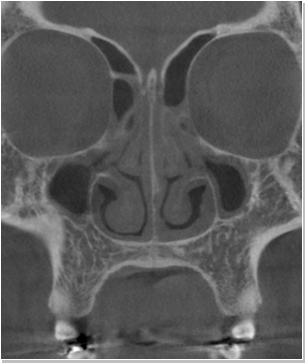

비염

비중격만곡증

축농증